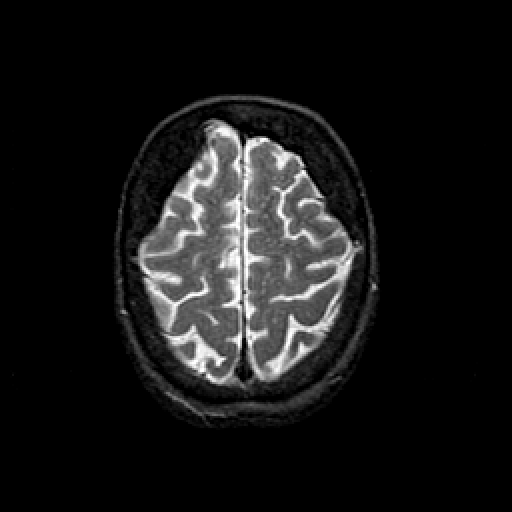

T2-weighted structural MR: Slice 43

Slice 43